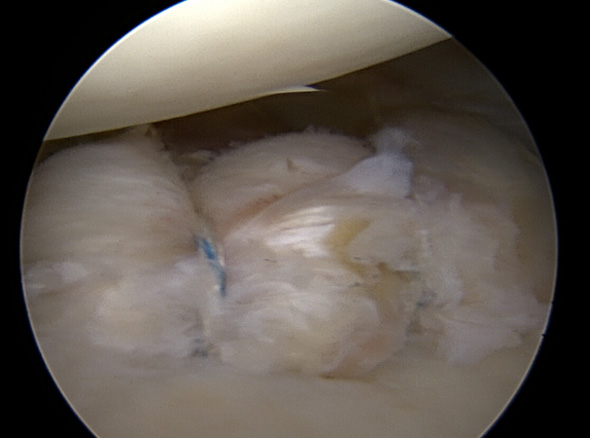

관절 내시경을 통해 파열된 관절와순을 정상적인 모양으로 봉합하여 제 기능으로 회복시켜 줍니다.

관절 내시경을 통해 늘어나 있는 관절낭을 알맞은 긴장도를 갖도록 봉합하여 줍니다.